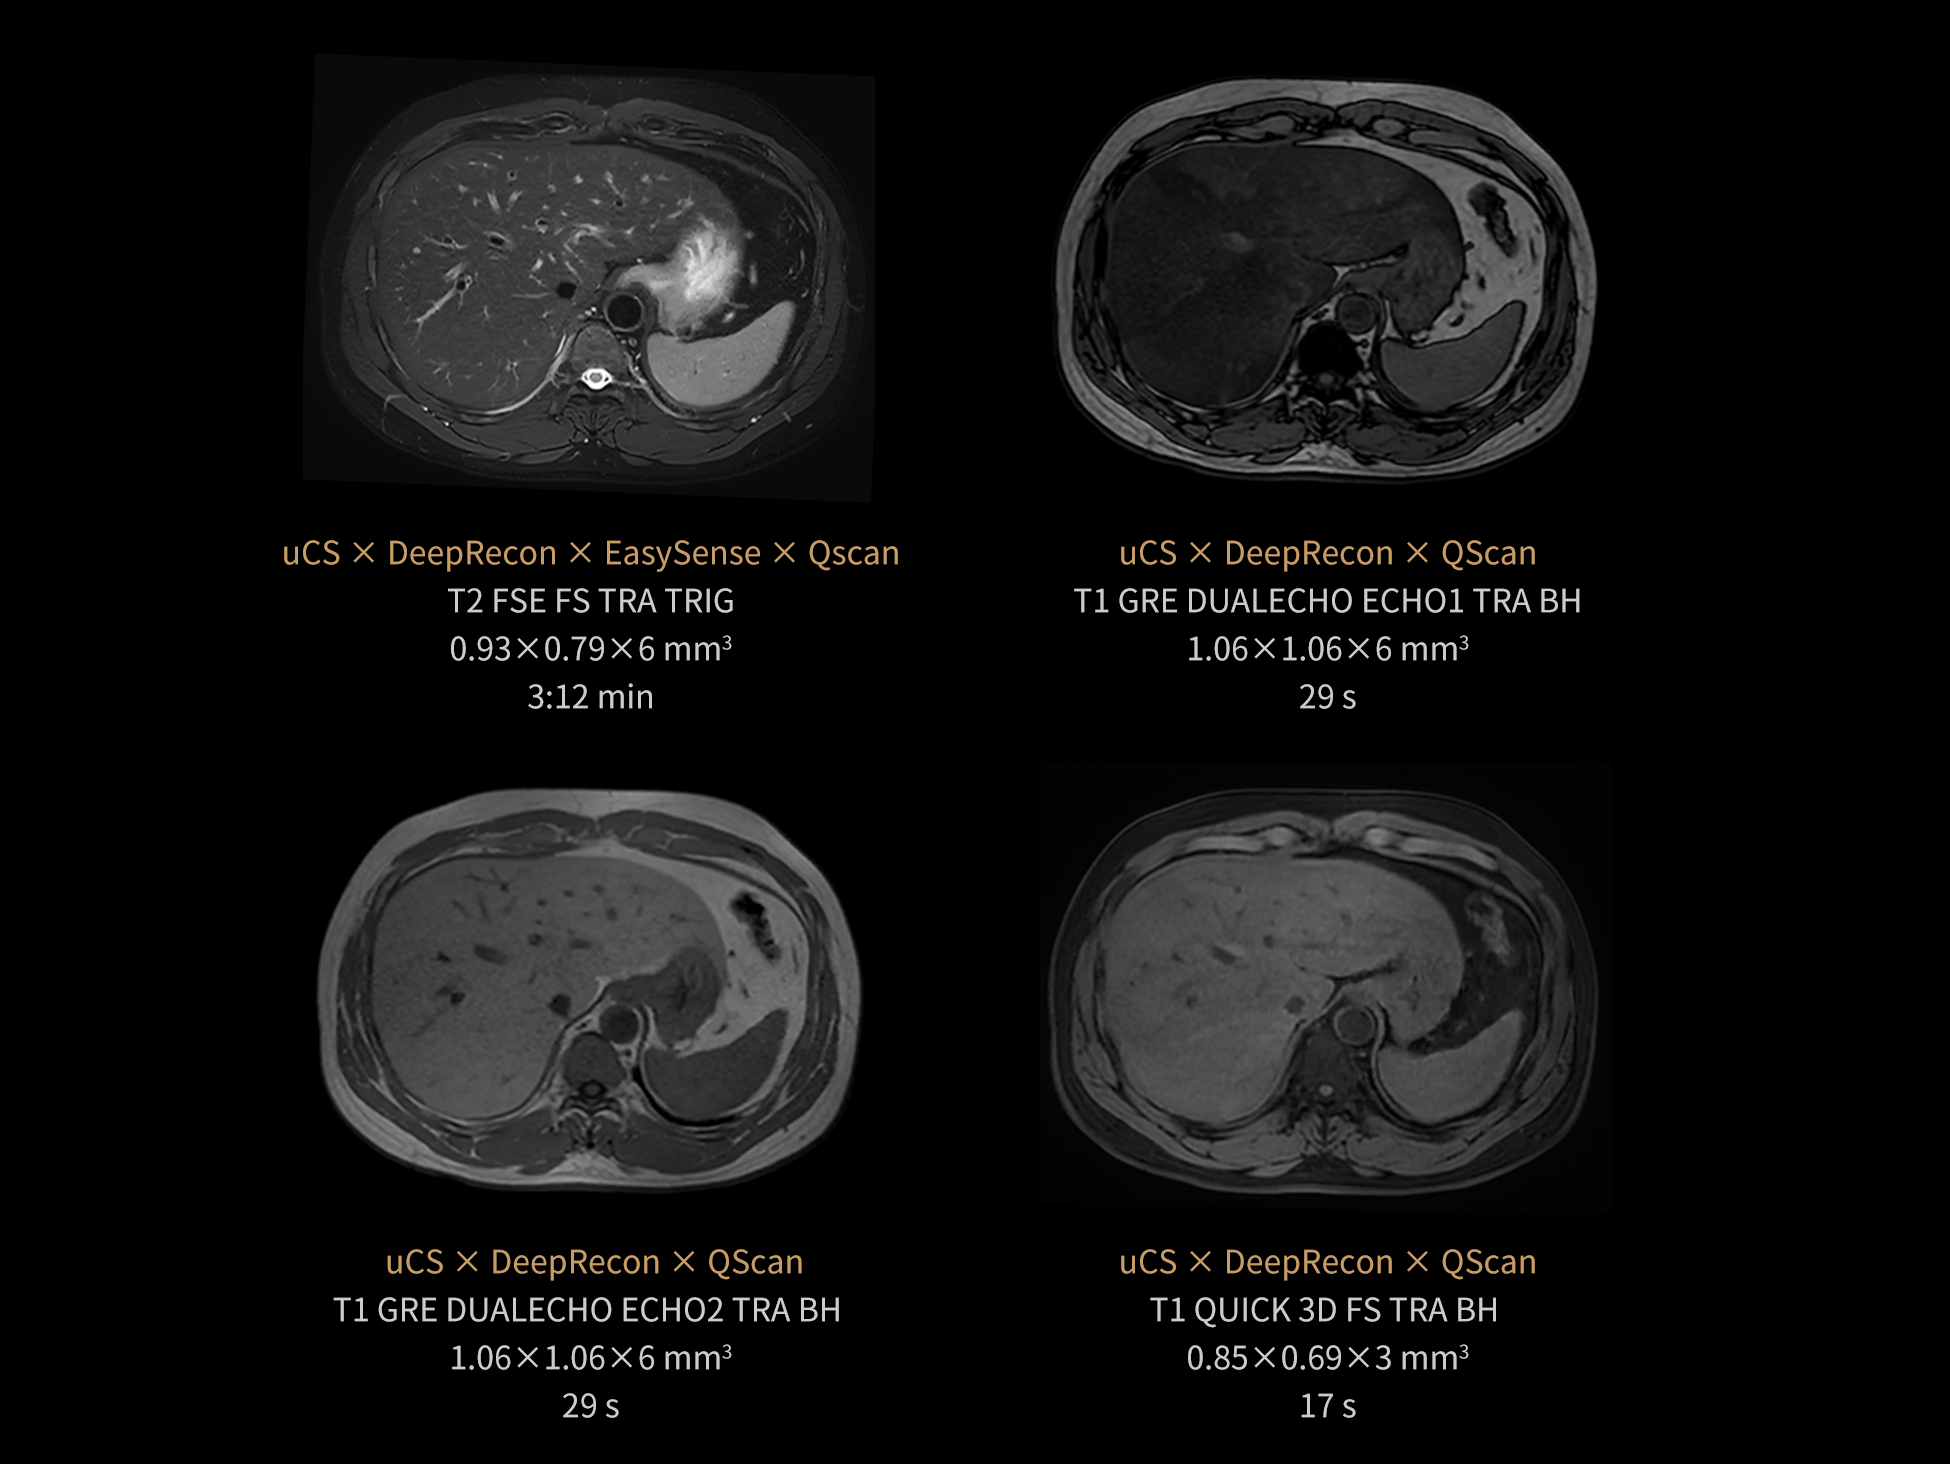

The combined use of uCS, DeepRecon, QScan, and EasySense within the uAIFI Technology platform addresses key pain points in abdominal magnetic resonance imaging, such as artifacts and prolonged scan durations. This integration achieves an optimal balance of "noise reduction, rapid scanning, and free-breathing," enhancing the effectiveness and efficiency of abdominal MRI.

Images courtesy of United Imaging.